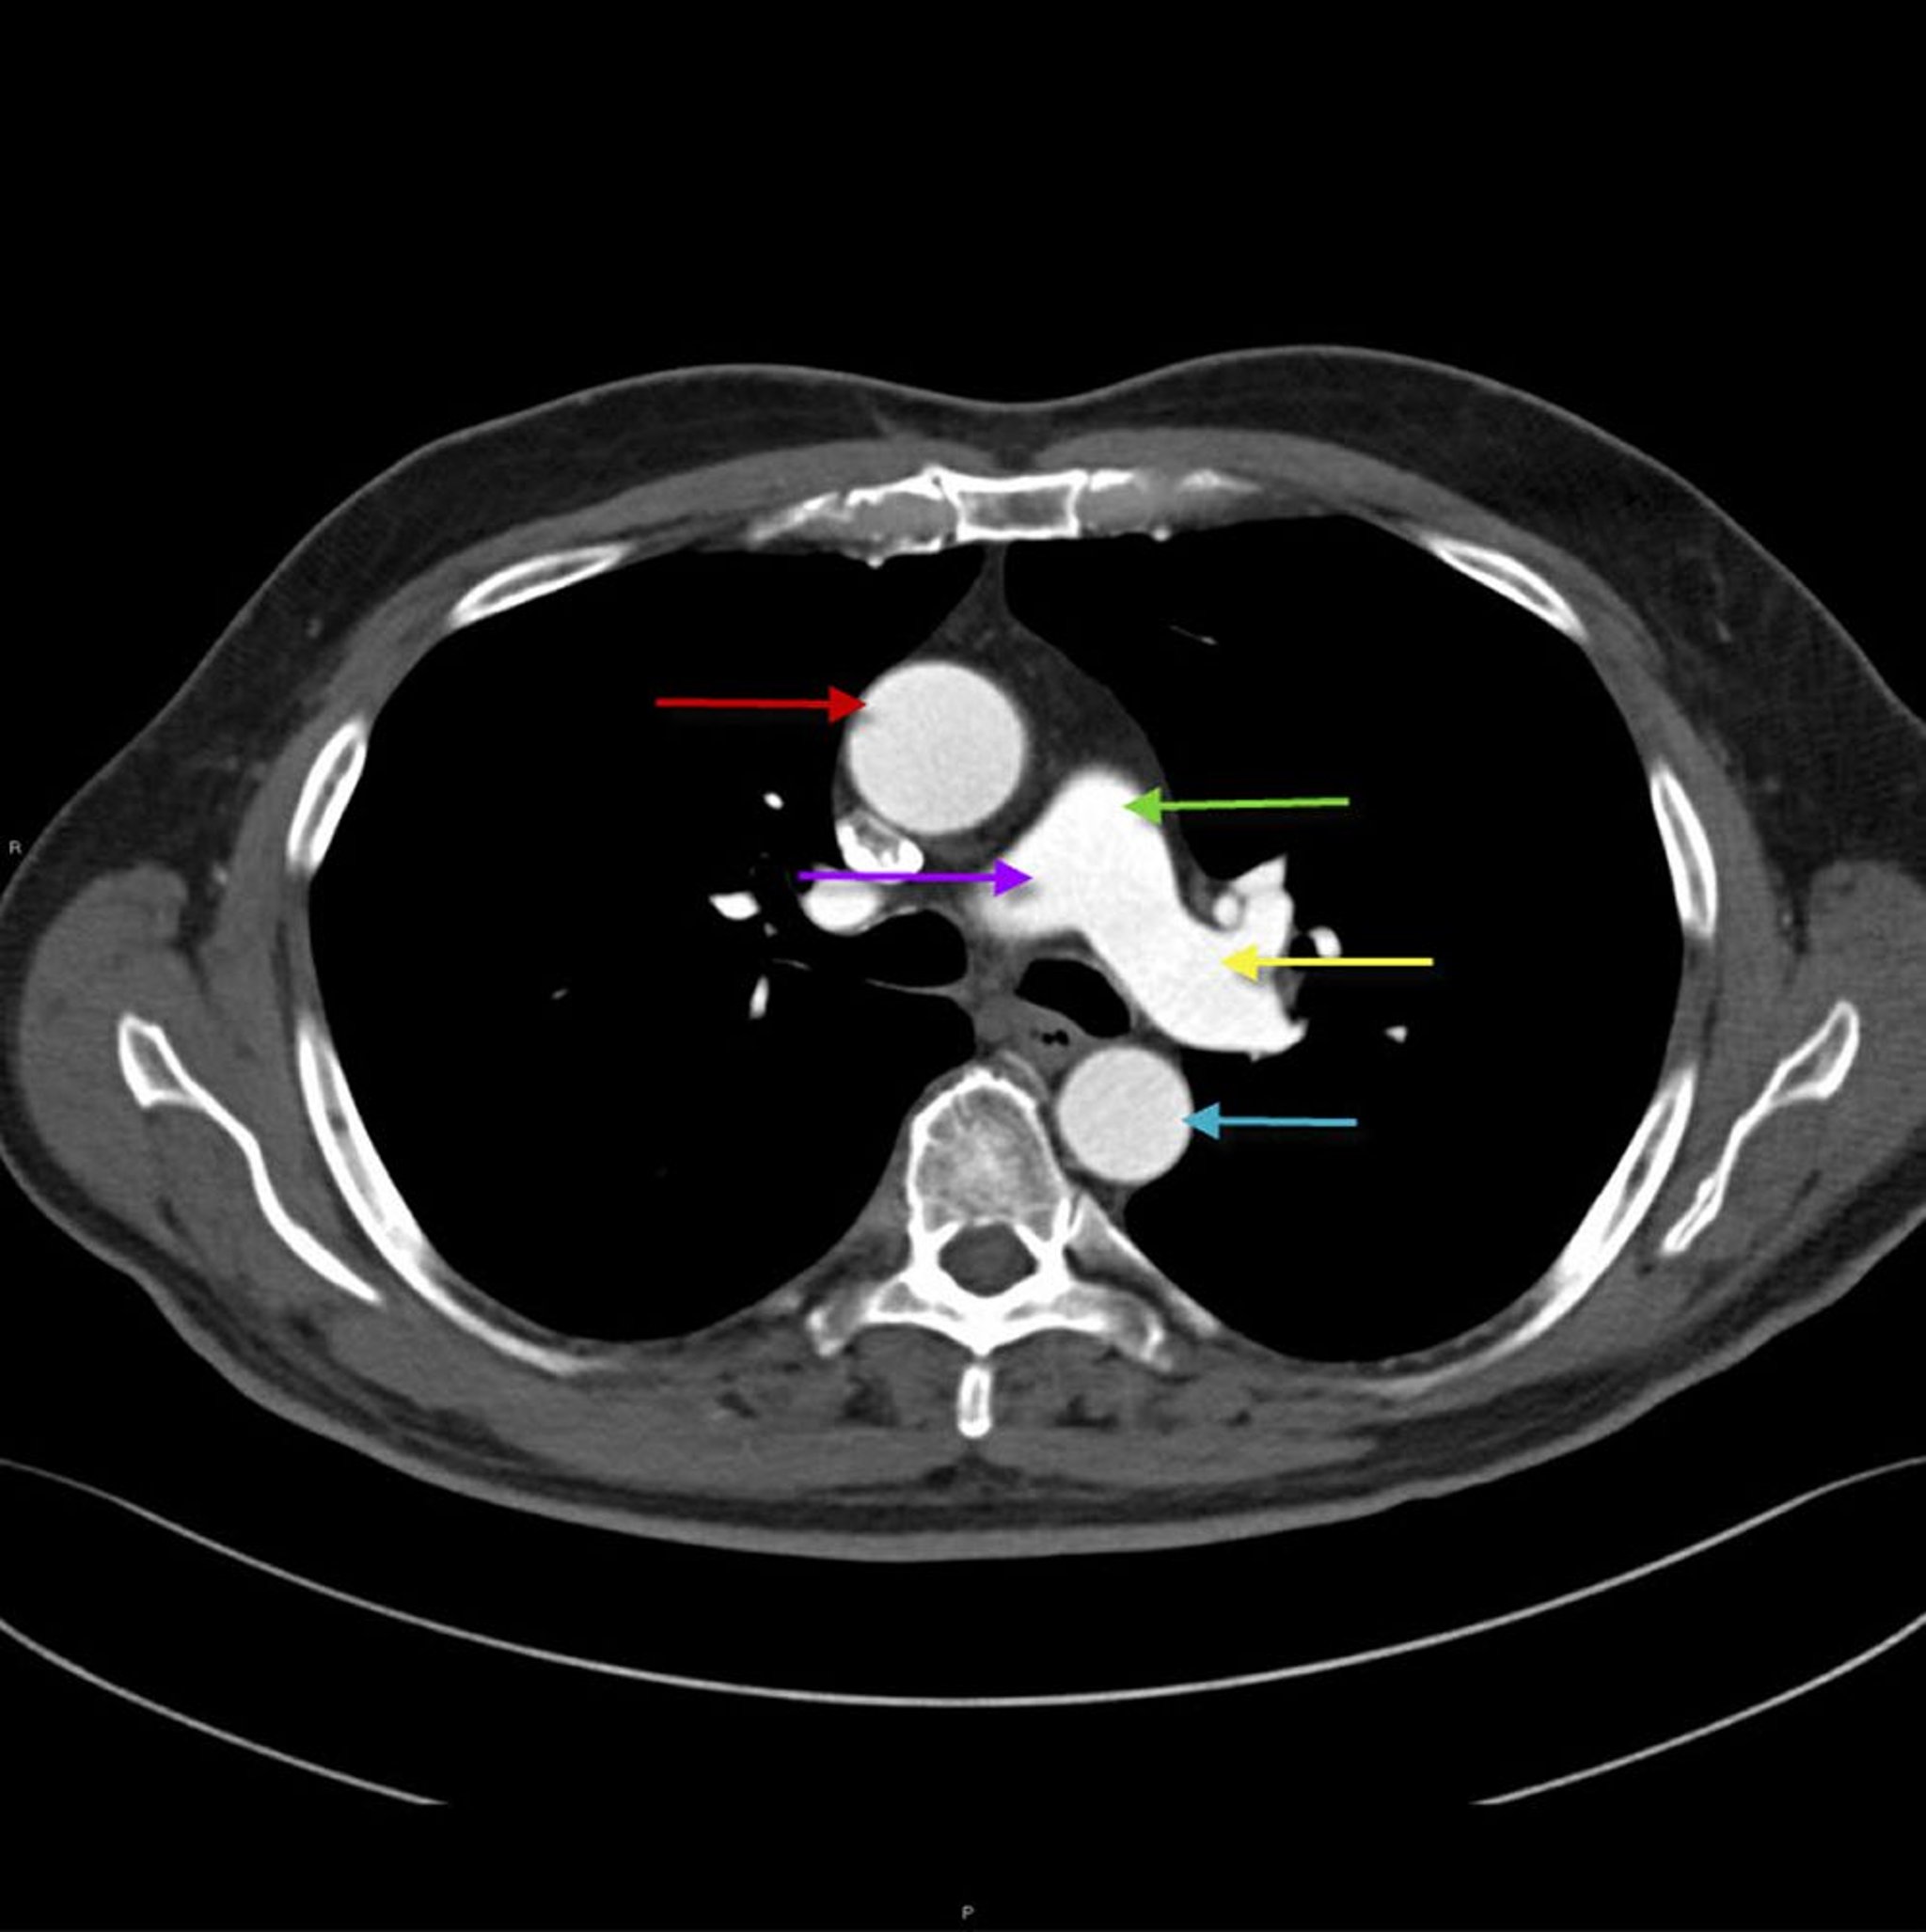

CT lồng ngực cho thấy giải phẫu của động mạch chủ và động mạch phổi

Hình ảnh này cho thấy động mạch chủ ngực lên (mũi tên màu đỏ) với động mạch chủ ngực xuống (mũi tên màu xanh lam). Động mạch phổi chính (mũi tên màu xanh lá cây) chia thành động mạch phổi phải (mũi tên màu tím) và trái (mũi tên màu vàng).